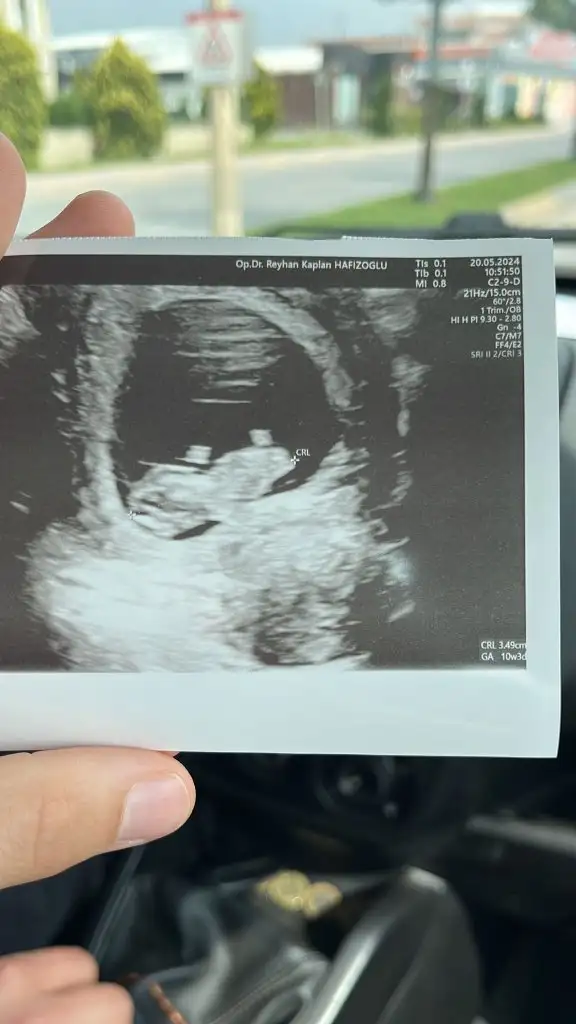

merhaba bana da bakabilir misin . karından . 10+1 . :)Kız gibi

Kız gibimerhaba bana da bakabilir misin . karından . 10+1 . :)

teşekkür ederimmm yorum için :)Kız gibi